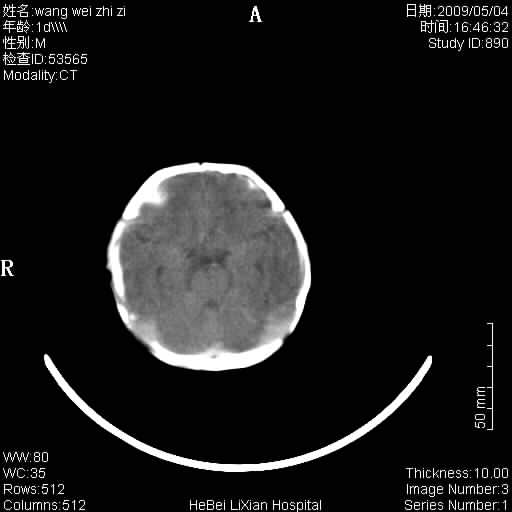

患者,男,1天,上肢抽动数次伴气促.有急产史.可以诊断珠网膜下腔出血吗?

局部5毫米薄层扫描

考虑 缺氧缺血性脑病伴蛛网膜下腔出血,可疑左侧硬膜下积液

支持,至少双侧外侧裂比较像,缺血缺性脑病有待进一步考证,建议治疗后1到2周复查